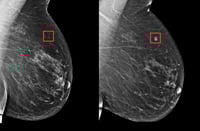

La inteligencia artificial IA podría disminuir la cantidad de cánceres de mama que se identifican entre una mamografía y otra de acuerdo…